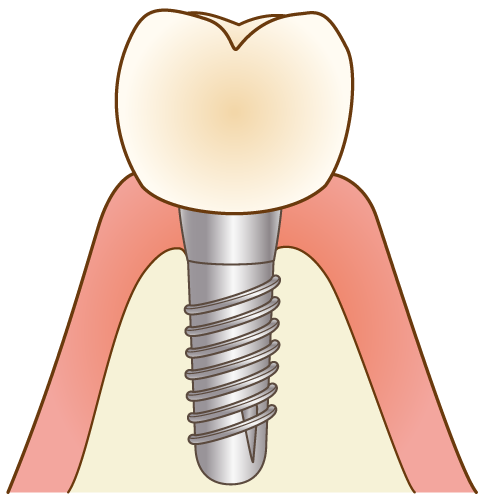

7人工歯の作製・取りつけ

型取りをして、人工歯を作製し、取り付けます。

型取りをして、人工歯を作製し、取り付けます。

最終的な被せ物の材質に関しましては、個々の患者様の咬み合わせの状態、清掃性や審美性の確保を考慮し、セラミックあるいはジルコニア、ゴールド(白金)などの選択肢の中から歯科医師がご提案致します。